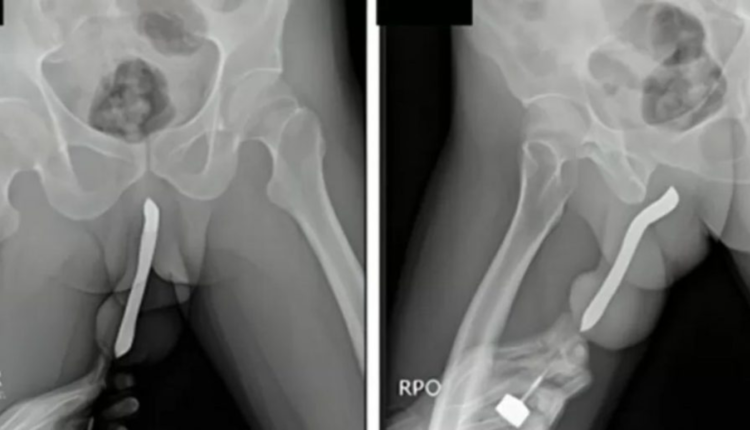

O incidente, ocorrido durante um ato sexual, envolveu a quebra da escova de dentes dentro de seu órgão genital, uma ocorrência tão bizarra quanto perigosa. Esse episódio levanta questões sobre os extremos que alguns indivíduos exploram em busca de satisfação sexual. O relatório médico detalha a extração cirúrgica do objeto e a subsequente recuperação do paciente, um processo que, por pouco, não resultou em consequências mais graves.